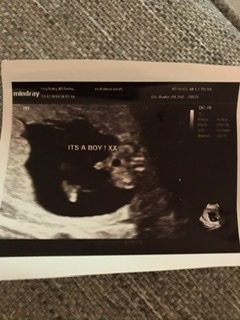

Just had my 20 week scan today. They went through all the organs. No concerns. Also found out we're having a boy!!!! Everyone is so excited! Can finally start referring to baby by name!

Missgemini · 15/01/2020 19:22

@AmyMaria2 wow what a confusing day!! First off so glad everything is ok that is the main thing! It happened to my friend she was told girl at private had a gender reveal and then at 20 week was told boy! I had my gender scan the same date as you however you can clearly see what I'm guessing is the penis In my pic whixh I've uploaded now, which you can't as much in the pic you've uploaded. I've been calling bump by name so must be such a strange feeling for you finding out it may be a girl! However aslong as they're healthy last all that matters! Can't wait for mine!

@AmyMaria2 here’s my baby boys gender pic from our private scan....his penis is quite visible 🙈 hope you can get a clear answer from your next scan x